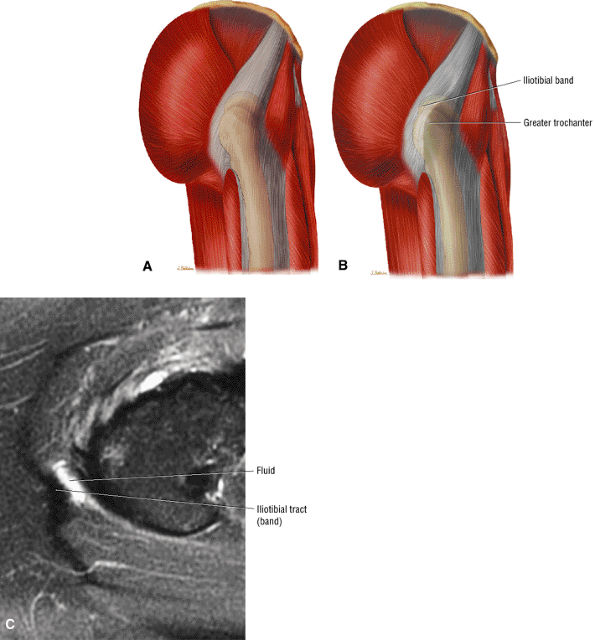

or secondary to communication with the hip joint. Trochanteric bursitis suspected on coronal images is confirmed on axial images.